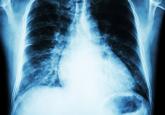

The ABCs of managing systolic heart failure: Past, present, and future